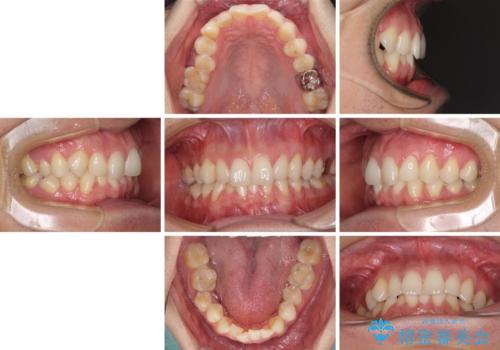

ディープバイトと叢生 インビザラインによる矯正治療

- 前歯のディープバイトと叢生を気にして来院された患者様です。

目立ちにくい装置を希望されていたため、ワイヤー装置とインビザラインを提案したところ、インビザラインを希望されました。

上下ともに叢生が認められたため、親知らずすべてを抜歯し、歯列全体を後方へ移動させることで歯列を整えることとしました。

上顎奥歯の銀歯も気になっていたので、矯正治療の途中でセラミッククラウンへ変更し、その後歯列を仕上げていくこととしました。

ディープバイトもデコボコも改善され、気になっていた銀歯もセラミックとなり、患者様には大変満足していただきました。